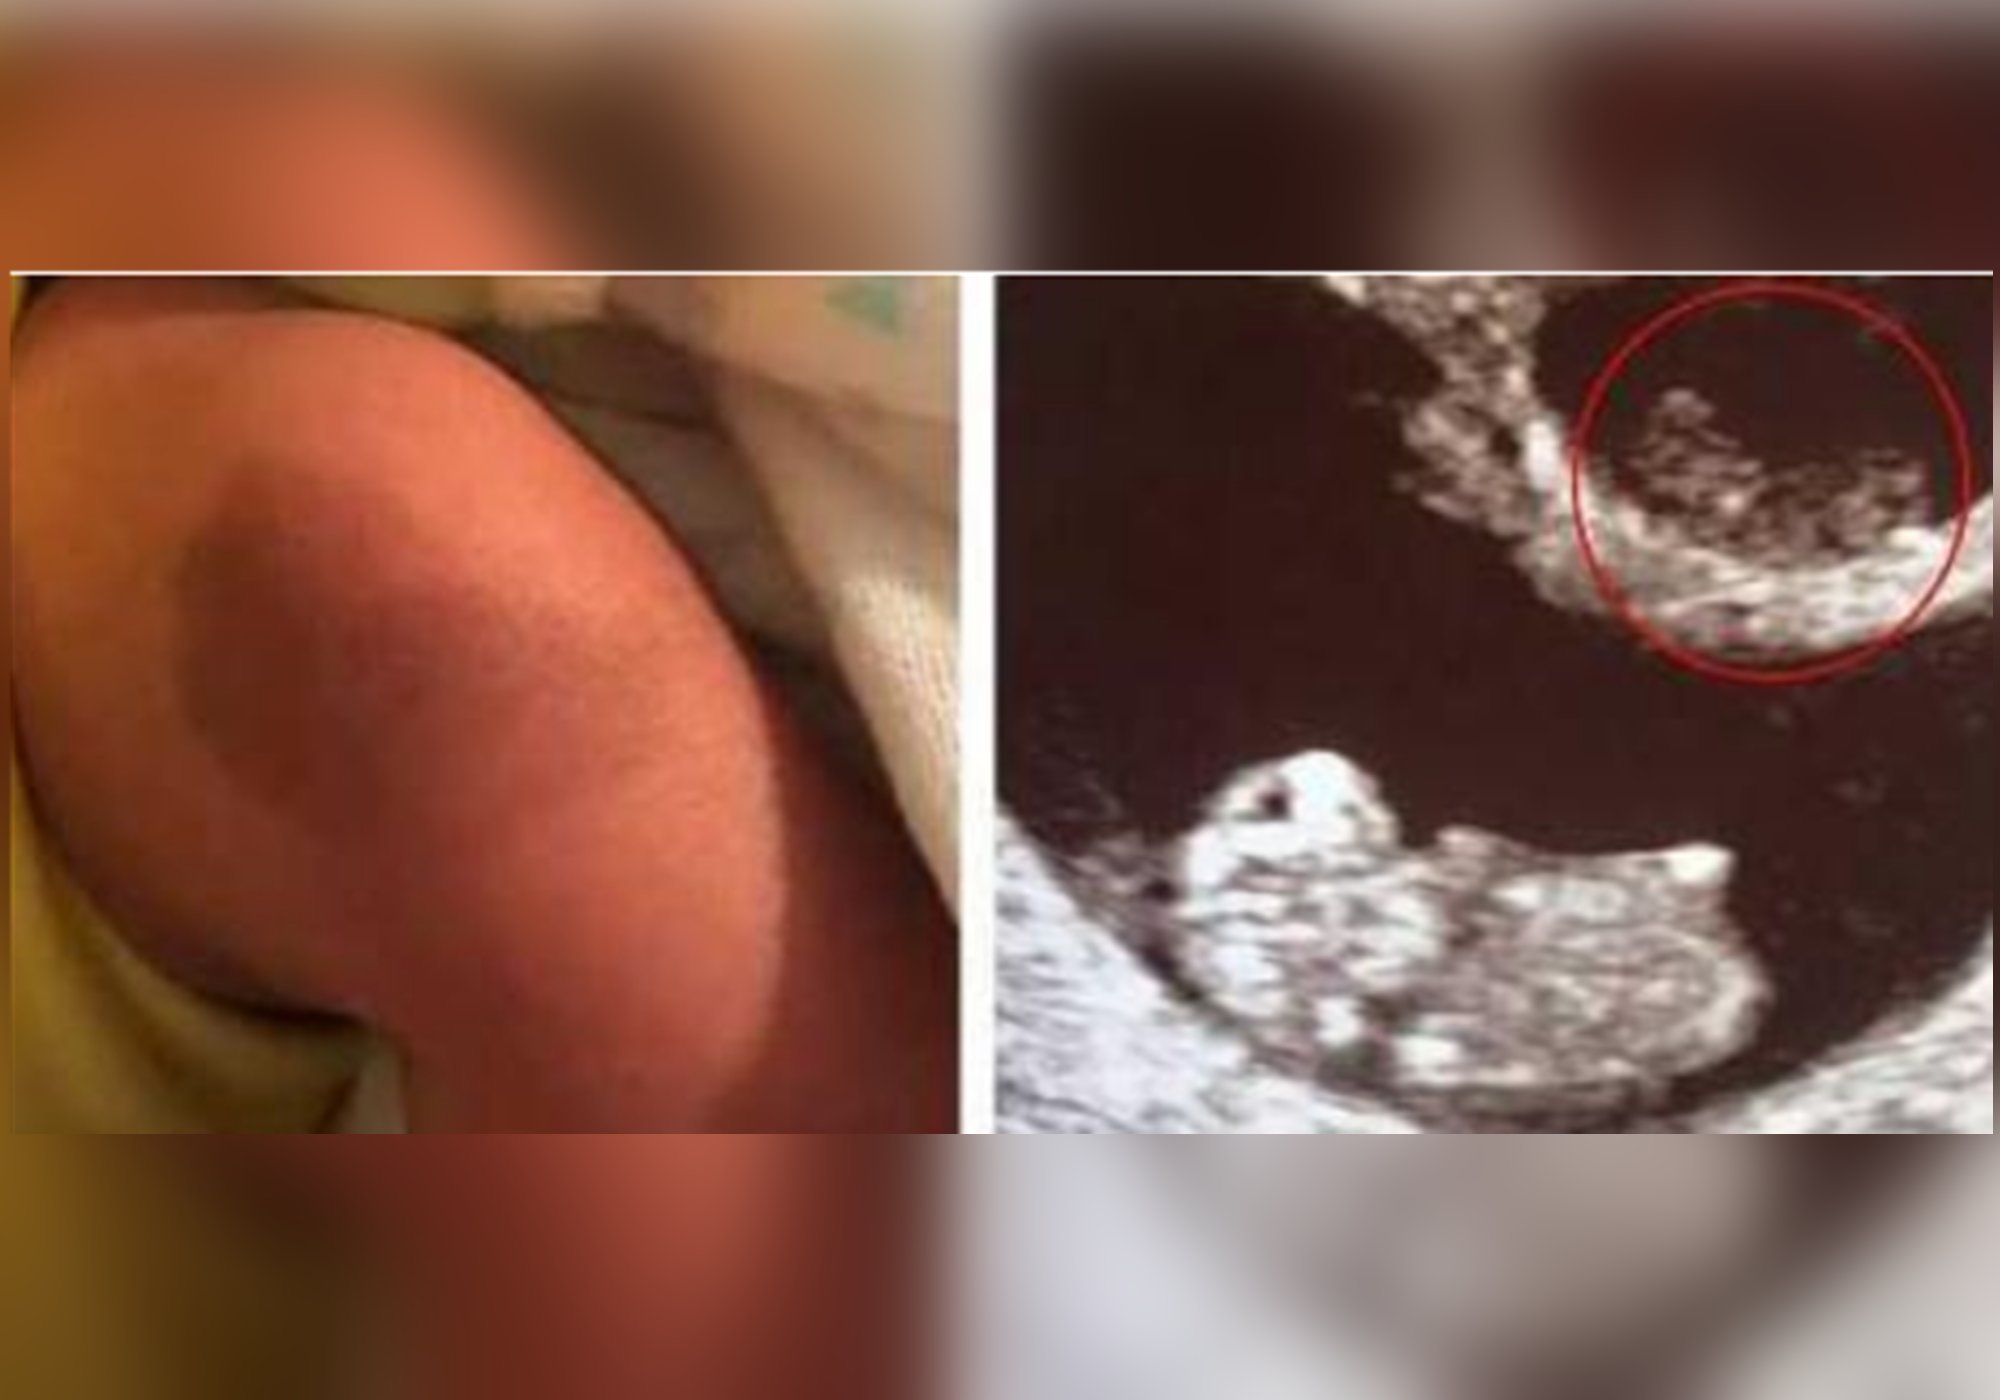

幸运的是,这位孕妈肚子里剩下的那个宝宝发育得很好,并且顺利地出生了。令孕妈感到惊讶的是在宝宝的大腿上居然有一个深色的胎记,并且这个胎记和当时孕检时消失的姐姐的影像非常相近。于是这位宝妈便把这个印记称之为爱的胎记,认为这是消失的姐姐为弟弟留下的礼物。

在医学上将双胎变成单胎的情况称之为双胎消失综合征。指的是在孕期的时候,双胎中的一个胎儿逐渐被另一个胎儿吸收的情况。

至于导致这种情况发生的原因,目前还没有一个确切的结论,不过有专家认为这是由于基因最原始的优胜劣汰的本能导致的。当机体发现胚胎发育有问题,质量不过关便会被流产,随后被母体或者是另一个胎儿吸收。